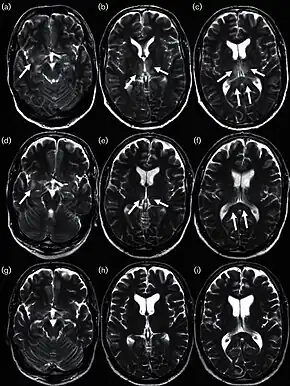

Influenza encephalitis MRI